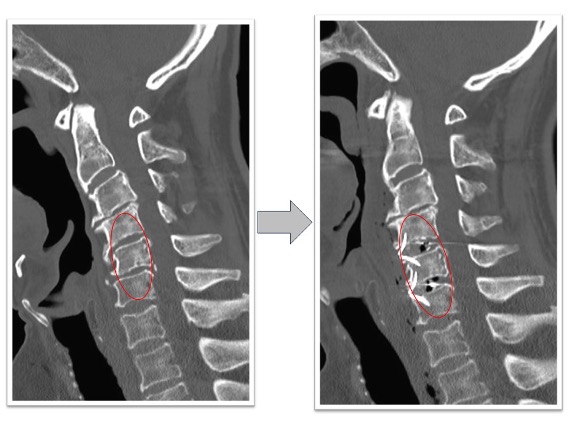

頚椎椎弓形成術実例(*患者様の許可を得て掲載しています)

頚椎症性脊髄症

上肢の運動障害、歩行障害の患者様に対して頚椎椎弓形成術を実施。術後MRI画像で頚髄の圧迫が解除され頚髄前後にスペースが生まれています(図赤丸)。また、CT画像では術前後の比較で脊柱管の前後幅が約1.5倍以上に拡大していることが確認できます(図青矢印)。術後は歩行安定し、上肢運動も改善しています。